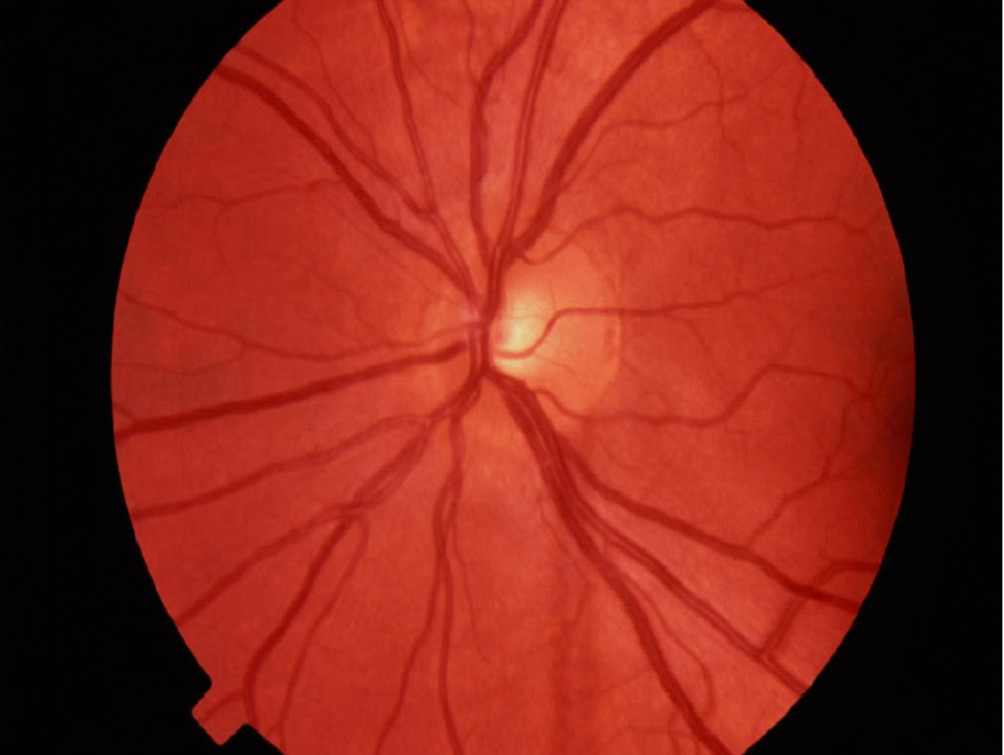

Fundus photography records digital photographic images of the back of the eye (the fundus). Specific parts of the fundus can be photographed such as the optic nerve and macula. Fundus photography compliments OCT in that it provides true color images of the different structures.

Normal Optic Nerve

Fundus photography allows documentation of changes to the optic nerve that occur glaucoma including cupping, disc hemorrhages, atrophy, and loss of the nerve fiber layer. Certain filters can be used to enhance the visualization the nerve fiber layer.

An example of an optic nerve with glaucoma damage imaged with both fundus photography and OCT and compared to the visual field in order to demonstrate the strucure-function relationship.

The lower half of the optc nerve has early damage, and this correlates with the small superior scotoma seen on the visual field test.